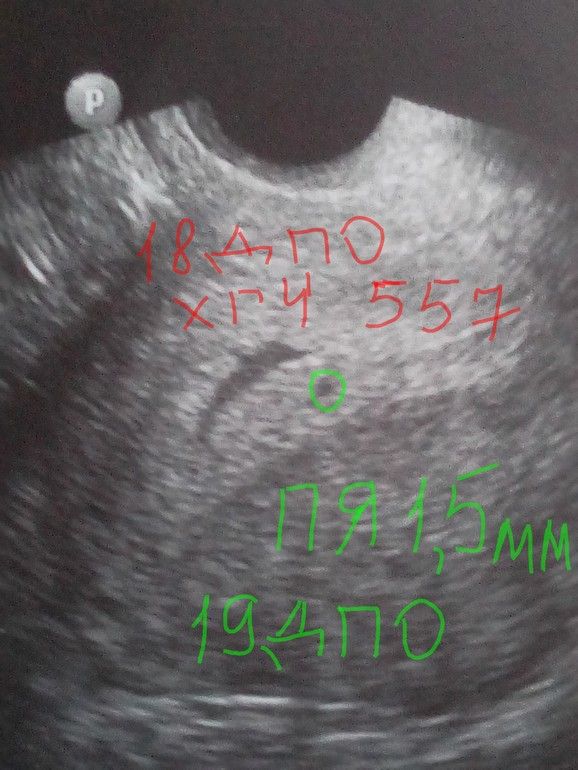

У вас только 9.10 хгч -54 был,а вы уже на 13.10 на УЗИ пошли? Ну зачем так рано туда бежать? Ну не увидят беременности ни маточной,ни внематочной,у вас хгч на данный момент максимум 300,если растет нормально,а пя видно при хгч от тысячи и то на хорошем аппарате и оно при таком хгч 3-4 мм

Рано пошли. У меня в 4 недели и 4 дня плодное яйцо было всего 1,5 мм, не каждый врач и не каждый аппарат увидит.

УЗИ показывает плодное яйцо, когда ХГЧ выше 1000, и то не факт. Нет смысла ходить так рано, а потом психовать, что ничего не увидели. Так можно и сразу после ПА идти, только зачем?

Конечно узи еще ничего не увидит. Узи видит только когда хгч 1000 и более. Не надо так рано бежать туда. Отслеживайте динамику хгч и потом повторите узи